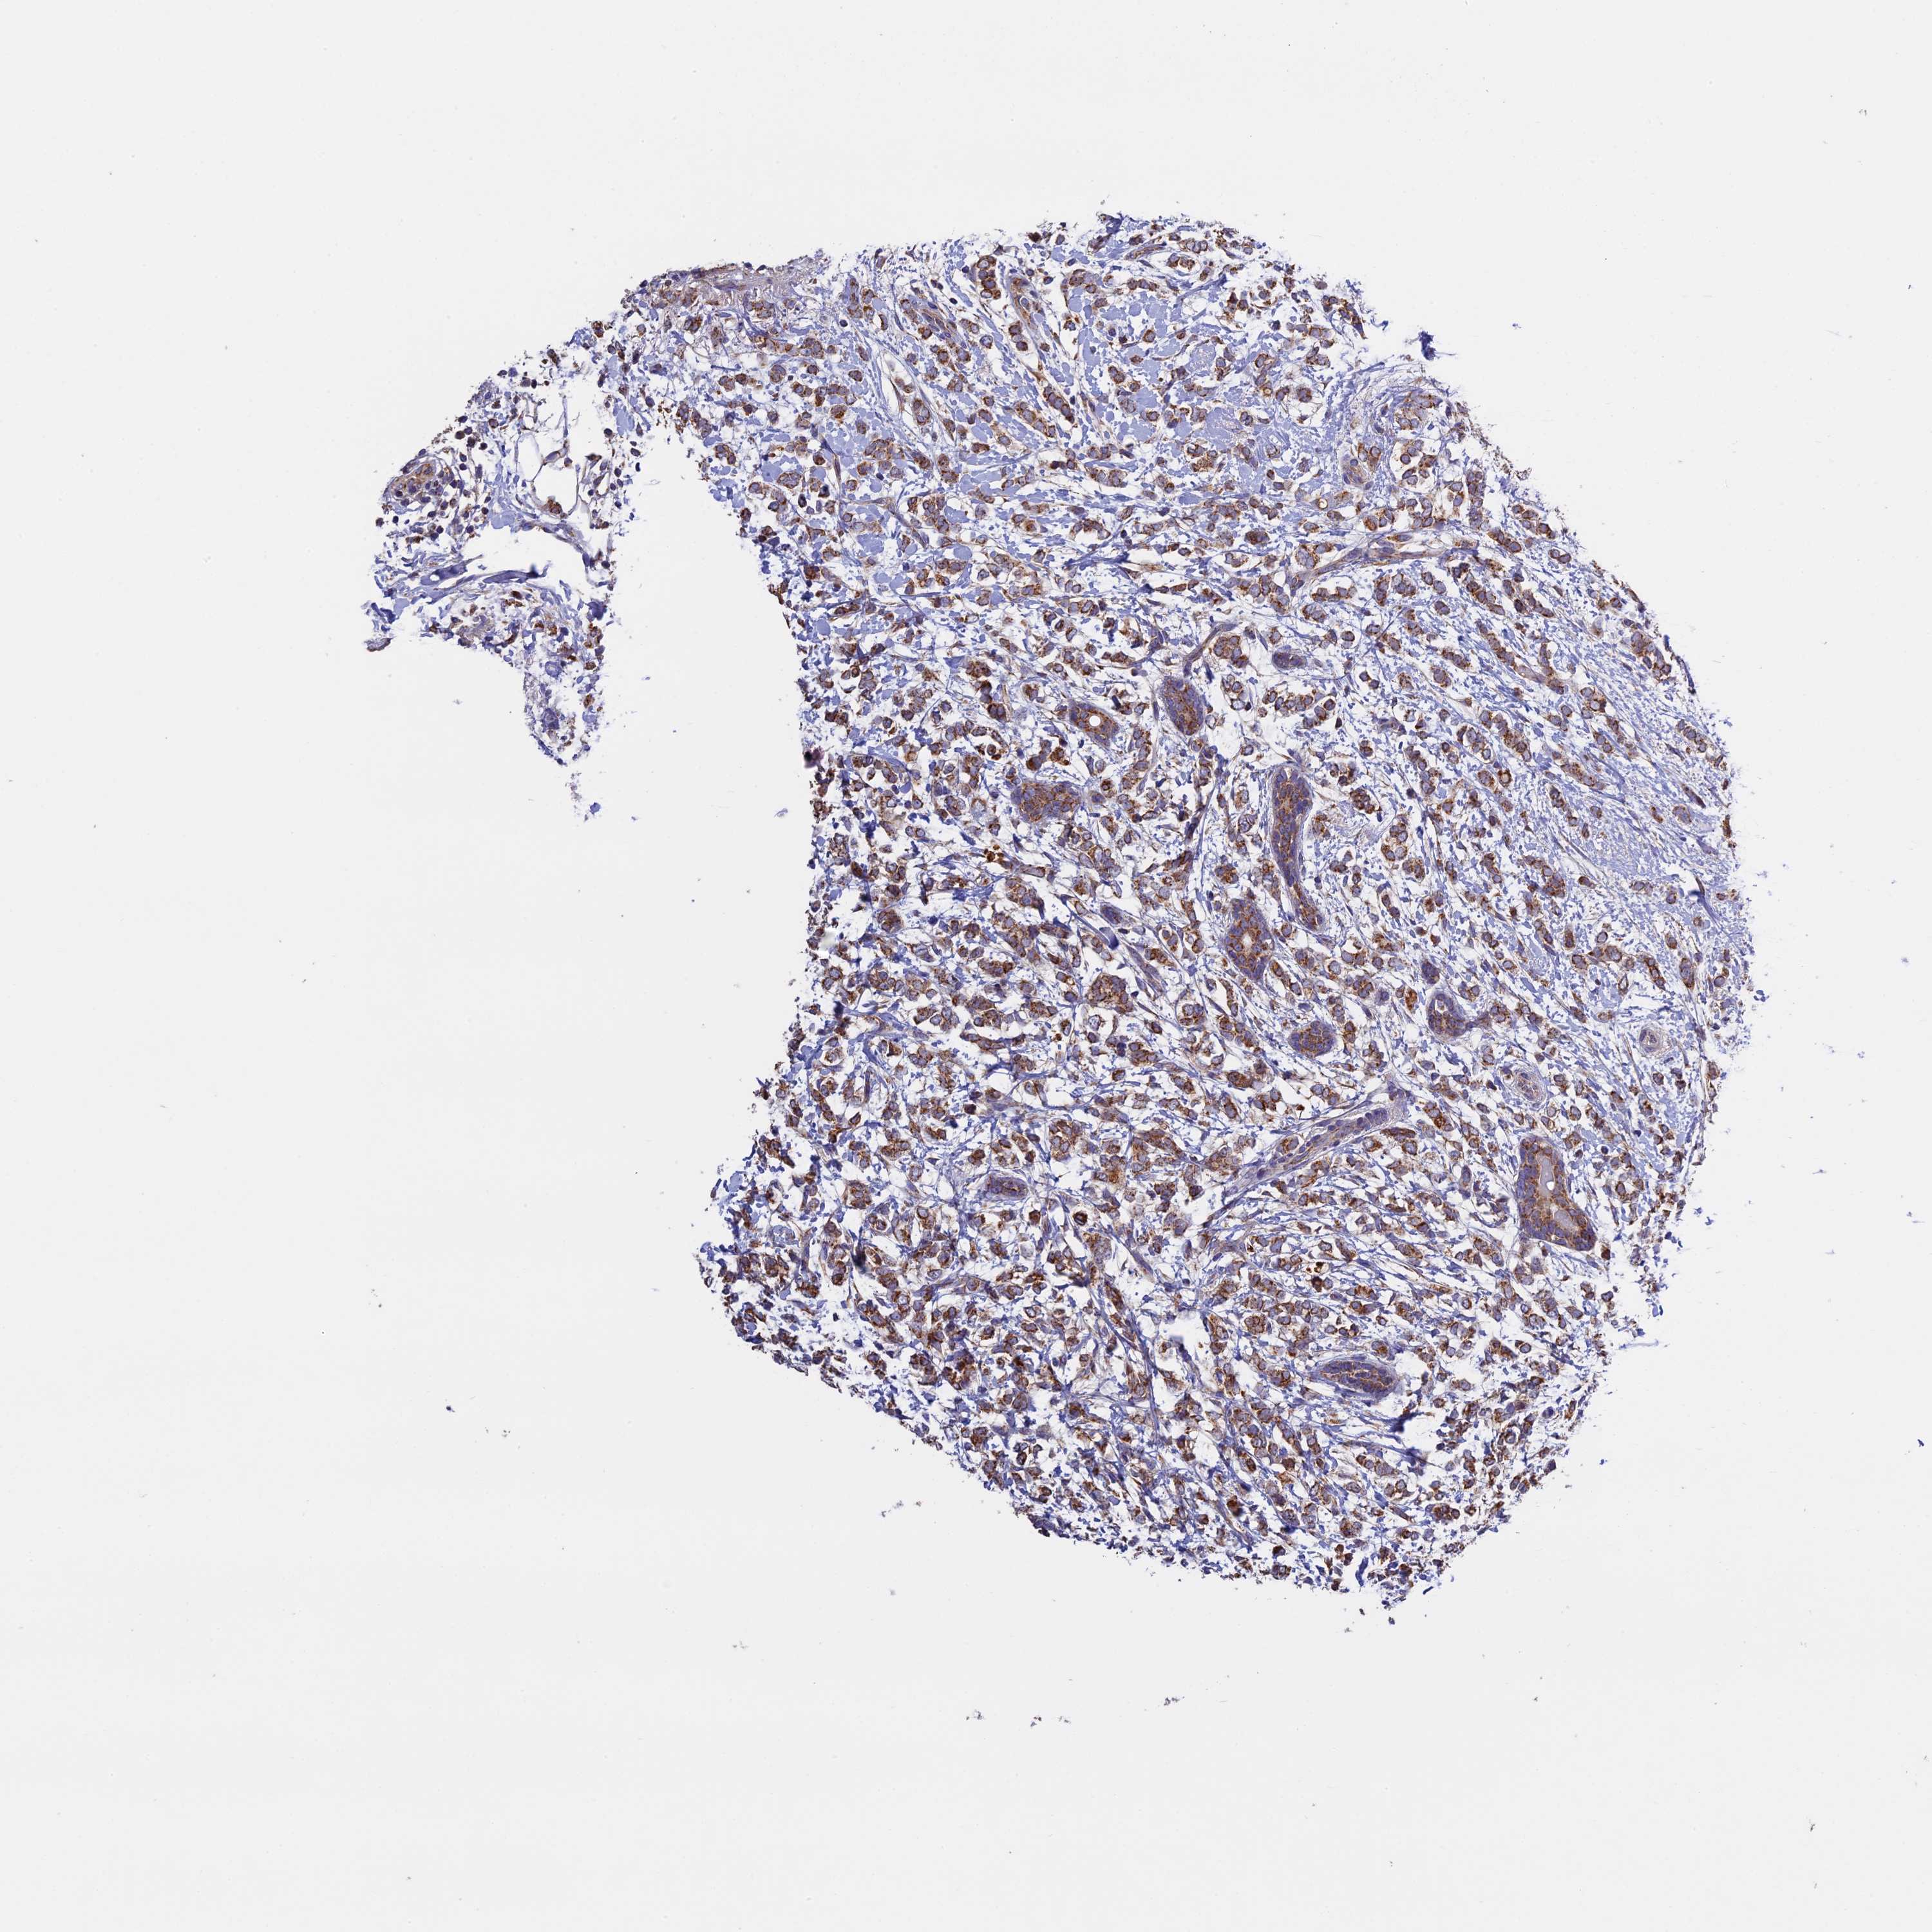

CANCER BREAST CANCER Show tissue menu

BRCA TCGA BRCA VALIDATION PROTEIN EXPRESSION